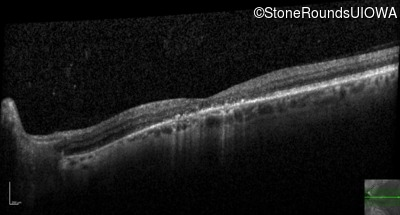

This 52 year old man had normal vision until his mid 30's when he began to have trouble distinguishing colors. the issuing 10 years he had a gradual loss of visual acuity accompanied by increasing photophobia.

| Age at visit: 61 years |

| Age at visit: 64 years |